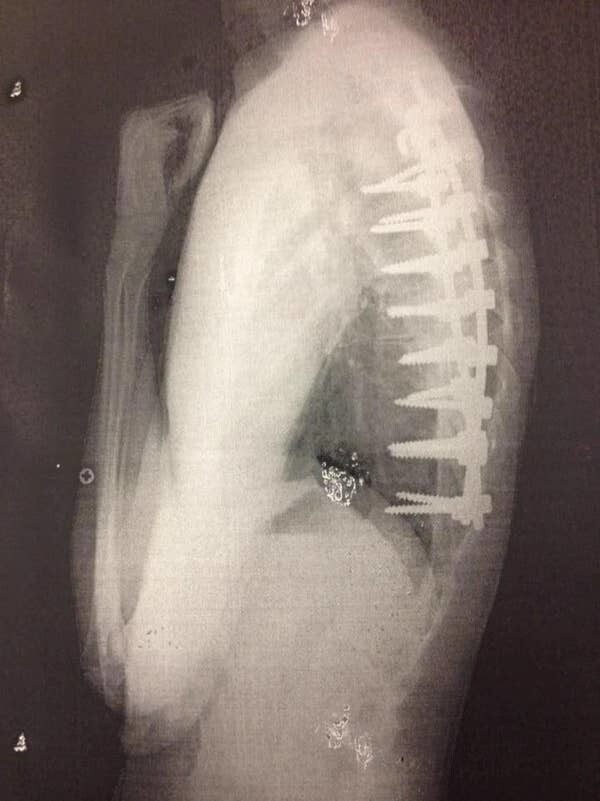

30. Для меня до сих пор дико, что в ходе операций на позвоночнике используют винты